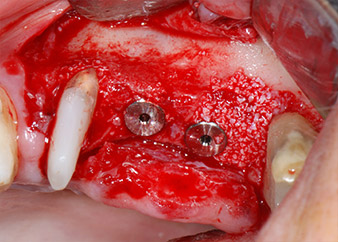

The implants (Restore, Keystone Dental, diameter 3,75 mm, length 8.0 mm) were placed with the implant motor (Figs. 11 and 12).

Low speed insertion of implant 26

Fig. 11: Low speed insertion of implant 26 with a torque limitation of 35 Ncm.

ready for the cover screws

Fig. 12: Both implants in place and ready for the cover screws.